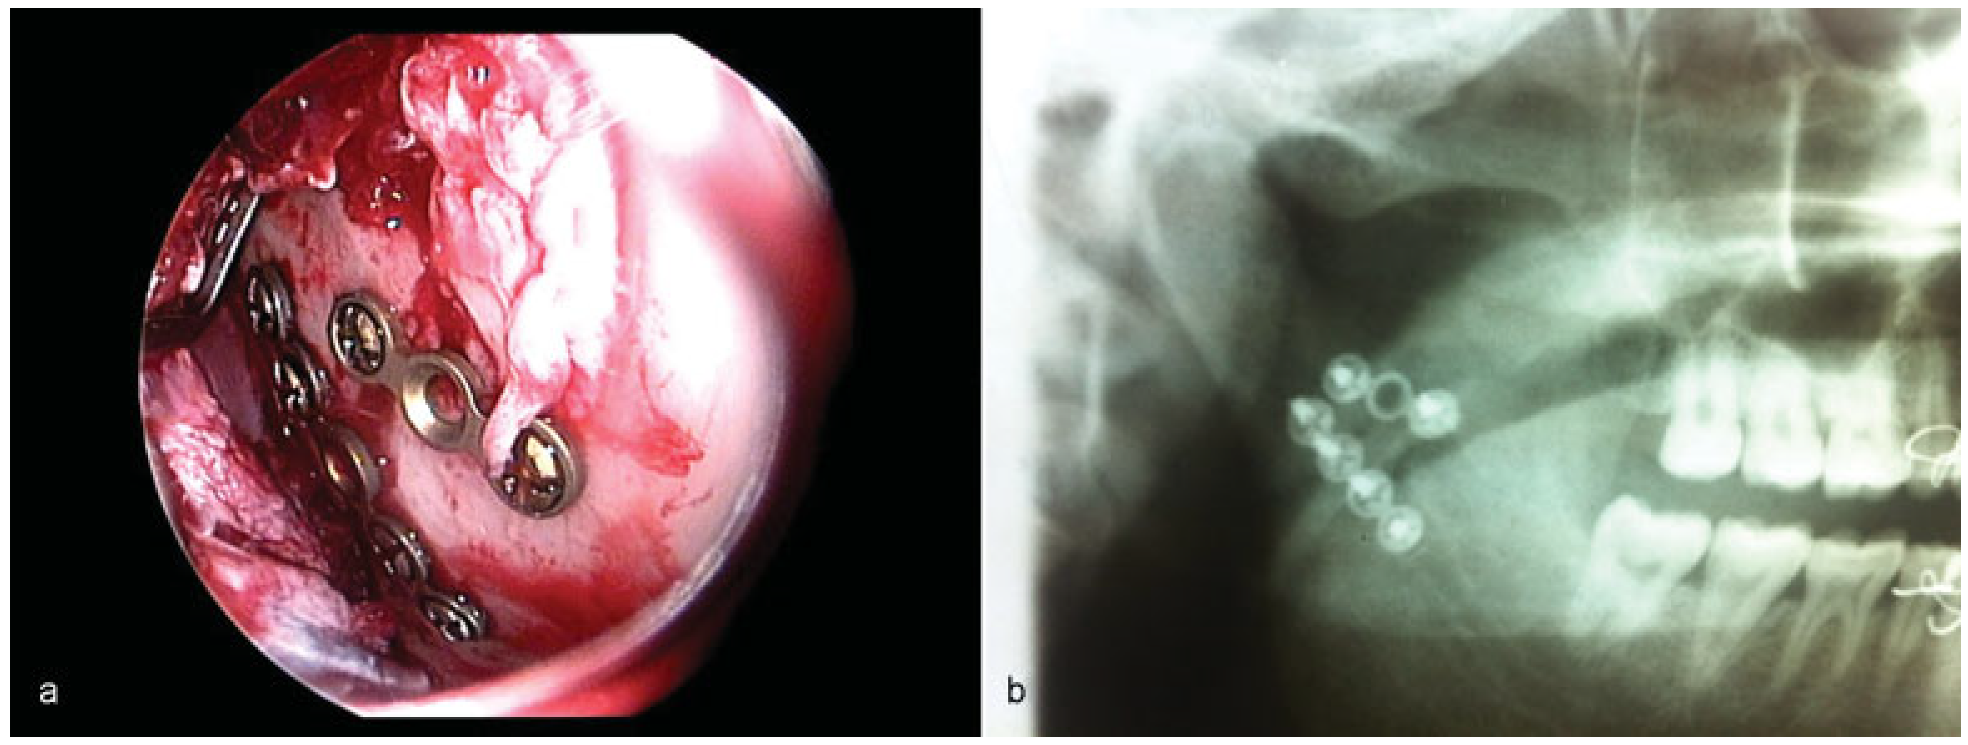

Figure 4.

(a) Endoscopic visualization of plates along the posterior aspect of lateral surface of subcondyle and another plate along the sigmoid notch. (b) Postoperative OPG shows the miniplate fixation.